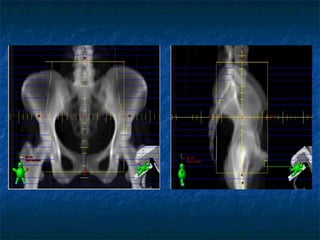

IMAGING For treatment planning purposes orthogonal radiographs/CT images are taken Images are transferred to Treatment planning system. If radiographs are to be used for planning then radiographs are scanned to transfer images to TPS. Catheter reconstruction done on TPS

IMAGING For treatmentplanning purposes orthogonal radiographs/CT images are taken Images are transferred to Treatment planning system. If radiographs are to be used for planning then radiographs are scanned to transfer images to TPS. Catheter reconstruction done on TPS